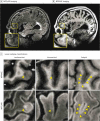

Design, setting, and participants: An observational clinical imaging study was conducted at an academic MS center. Participants included 36 individuals with MS (30 relapsing-remitting, 6 secondary or primary progressive) and 15 healthy individuals serving as controls. The study was conducted from March 10, 2010, to November 23, 2012, and analysis was performed from June 1, 2011, to September 30, 2014. Seven-Tesla MRI of the brain was performed with 0.5-mm isotropic resolution magnetization-prepared rapid acquisition gradient echo (MPRAGE) and whole-brain, 3-dimensional, 1.0-mm isotropic resolution magnetization-prepared, fluid-attenuated inversion recovery (MPFLAIR). Cortical lesions, seen as hypointensities on MPRAGE, were manually segmented. Lesions were classified as leukocortical, intracortical, or subpial. Images were segmented using the Lesion-TOADS (Topology-Preserving Anatomical Segmentation) algorithm, and brain structure volumes and white matter (WM) lesion volume were reported. Volumes were normalized to intracranial volume.

Results: Cortical lesions were noted in 35 of 36 participants (97%), with a median of 16 lesions per participant (range, 0-99). Leukocortical lesion volume correlated with WM lesion volume (ρ = 0.50; P = .003) but not with cortical volume; subpial lesion volume inversely correlated with cortical volume (ρ = -0.36; P = .04) but not with WM lesion volume. Total CL count and volume, measured as median (range), were significantly increased in participants with EDSS scores of 5.0 or more vs those with scores less than 5.0 (count: 29 [11-99] vs 13 [0-51]; volume: 2.81 × 10-4 [1.30 × 10-4 to 7.90 × 10-4] vs 1.50 × 10-4 [0 to 1.01 × 10-3]) and in cognitively impaired vs unimpaired individuals (count: 21 [0-99] vs 13 [1-54]; volume: 3.51 × 10-4 [0 to 1.01 × 10-4] vs 1.19 × 10-4 [0 to 7.17 × 10-4]). Cortical lesion volume correlated with EDSS scores more robustly than did WM lesion volume (ρ = 0.59 vs 0.36). Increasing log[CL volume] conferred a 3-fold increase in the odds of cognitive impairment (odds ratio [OR], 3.36; 95% CI, 1.07-10.59; P = .04) after adjustment for age and sex and a 14-fold increase in odds after adjustment for WM lesion volume and atrophy (OR, 14.26; 95% CI, 1.06-192.37; P = .045). Leukocortical lesions had the greatest effect on cognition (OR for log [leukocortical lesion volume], 9.65; 95% CI, 1.70-54.59, P = .01).